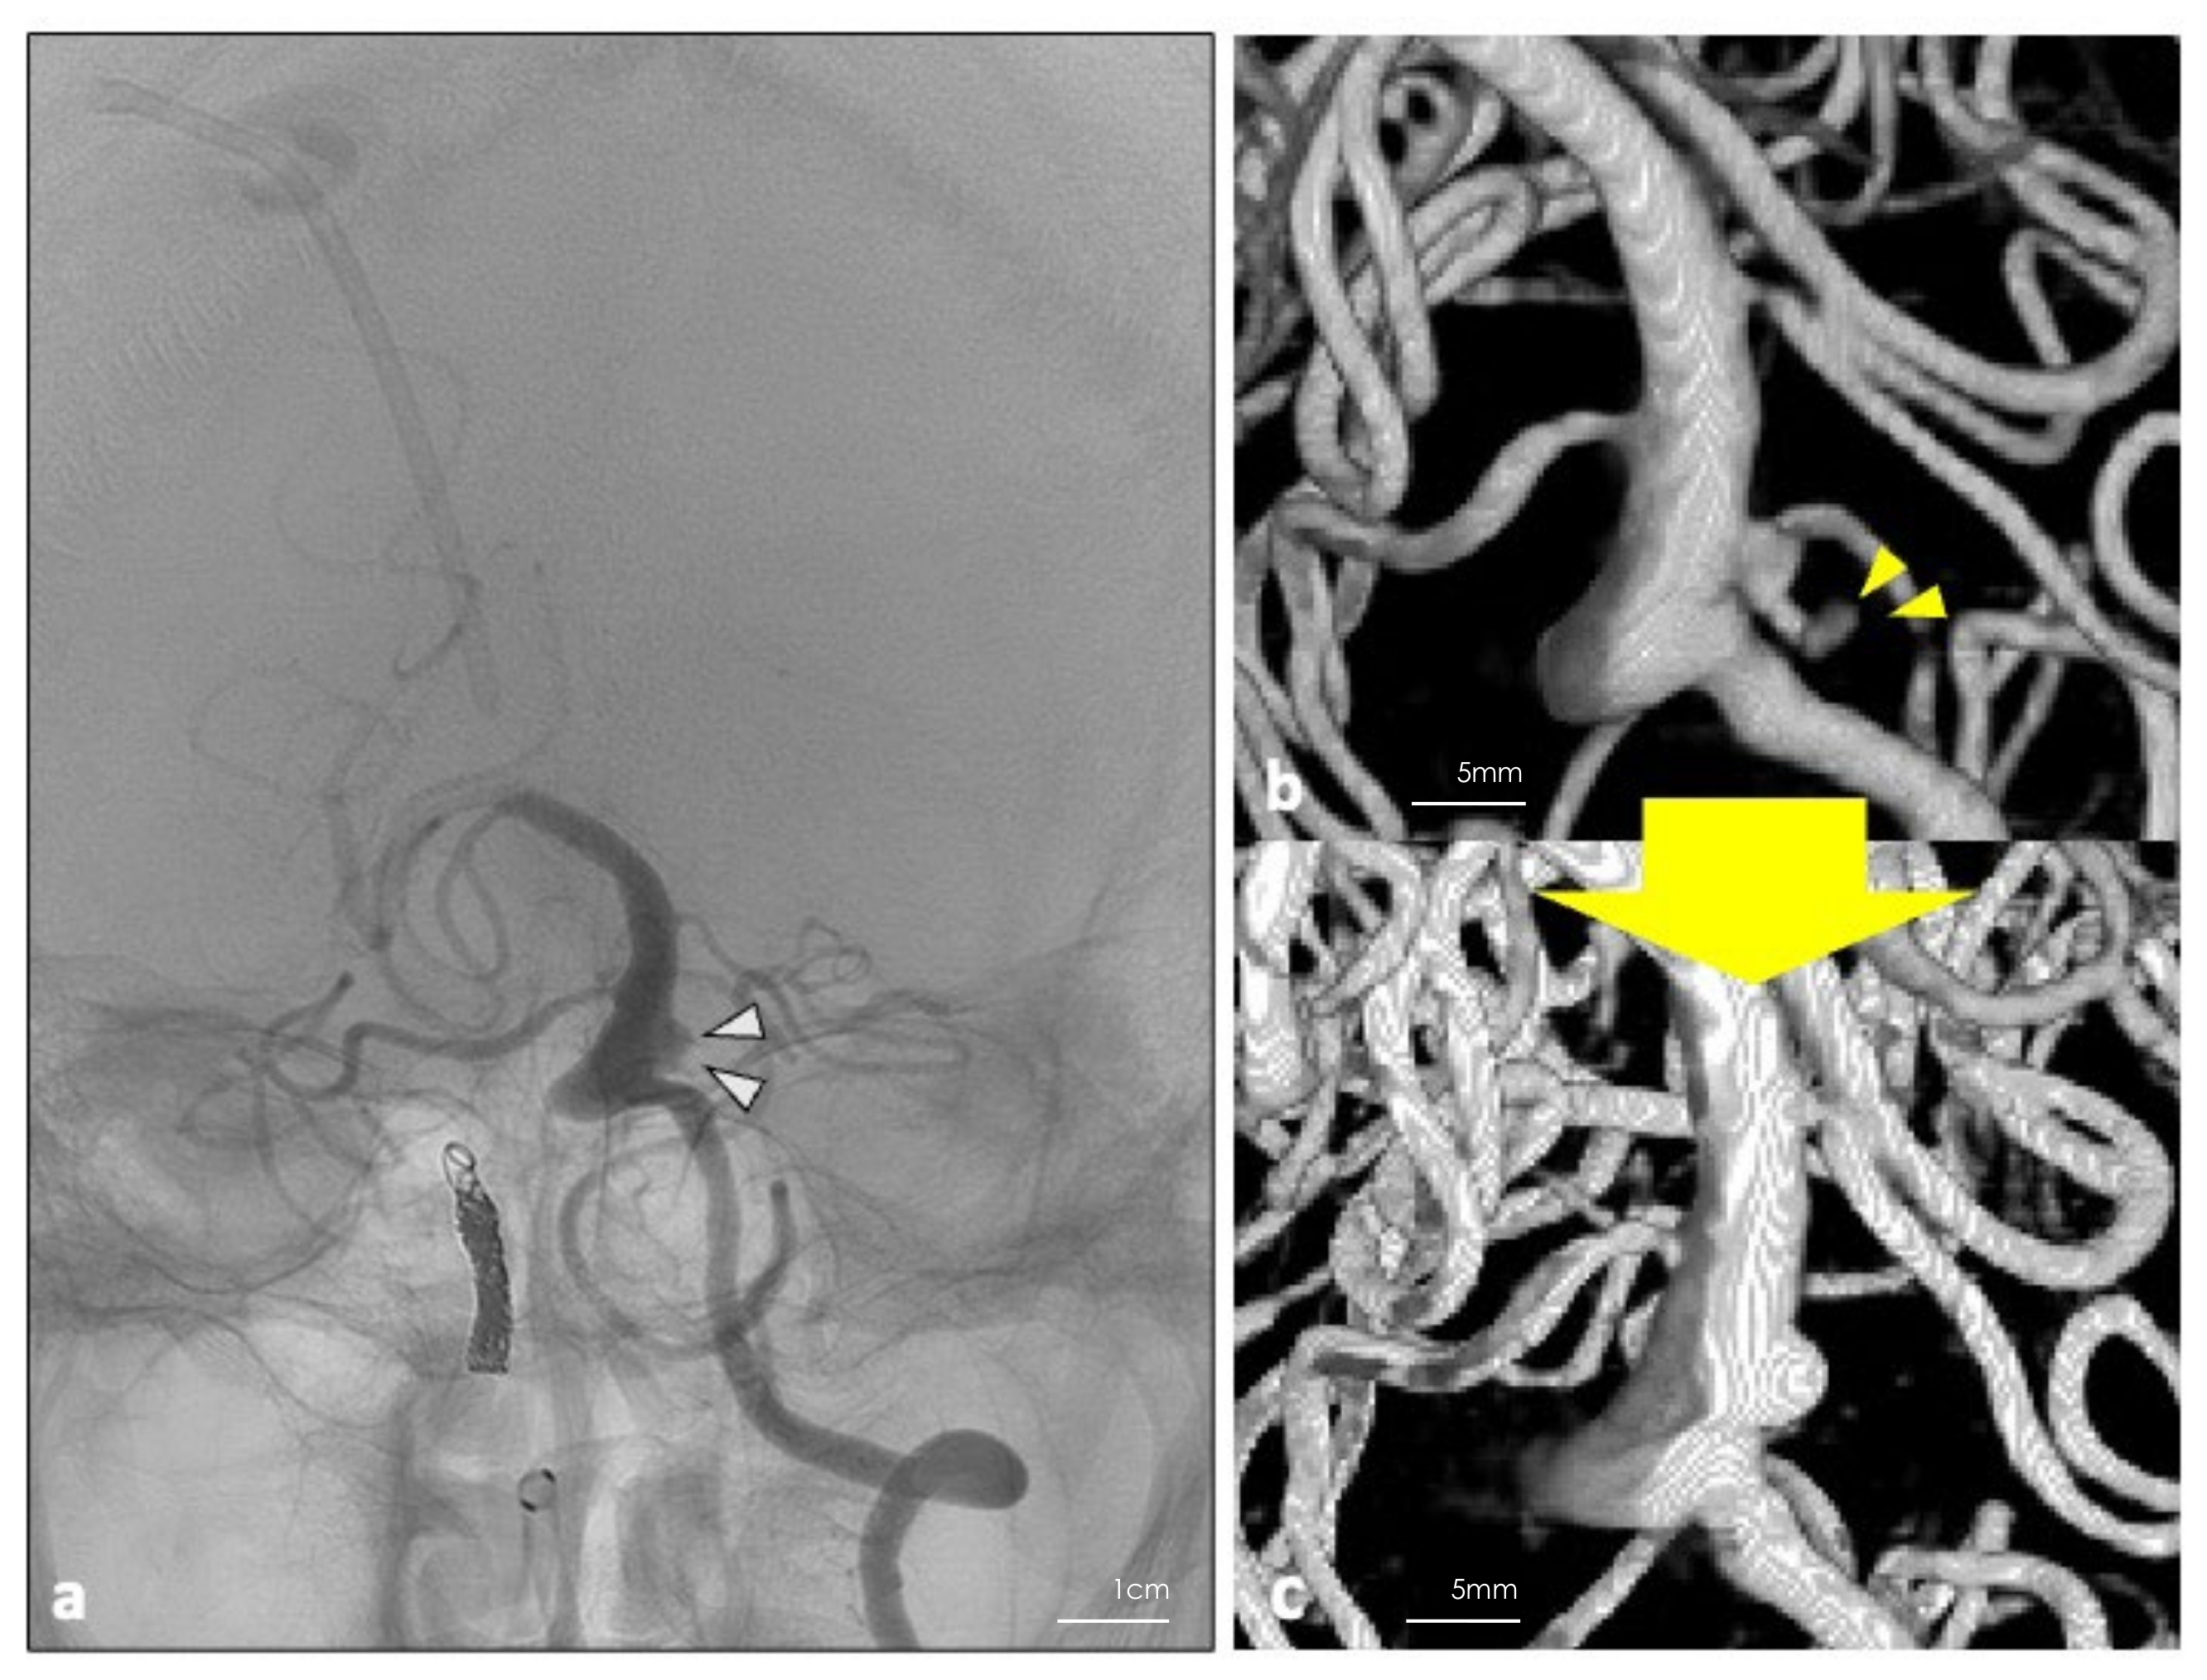

Figure 2.

(a) Operative view of the aneurysm. Yellow arrowheads indicate the location of the bleb. (b) The clip blade was aligned parallel to the basilar artery, avoiding the fifth cranial nerve. (c) Operative view after DuraGen was applied to the remaining dome. (d) The same area was covered with the patient’s fascia to make the wrapping multilayered. The layers were fixed with fibrin glue.

As expected, based on the preoperative imaging studies, we found the bleb, which we presumed to be the rupture point, on the lateral side of the aneurysm (Figure 2a). Careful inspection revealed that there was no perforator originating from the aneurysm. We applied an L-shaped titanium clip (Sugita #22, blade length 10 mm) to the rupture point. The blade was aligned parallel to the basilar artery, avoiding the fifth cranial nerve (Figure 2b). Finally, we applied DuraGen® (Integra Life Sciences Corp., Princeton, NJ, USA) to the remaining dome and covered the area with fascia so that the wrapping was multilayered. The layers were fixed with fibrin glue (Figure 2c,d). Occlusion of the rupture point and the patency of the parent artery and branches was confirmed with Intraoperative Doppler sonography, DSA, and Indocyanine Green video angiography.